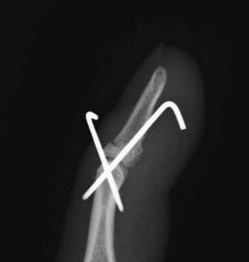

練習中にボールと指先にぶつけて受傷しました。レントゲン上、上の写真のような末節骨の骨折を認めました。このような骨折を骨性槌指(マレット変形)といいます。

手術は、鋼線を骨片がずれないように刺入し、もう1本の鋼線で関節を固定する「石黒法」という、この骨折の手術方法として、最もポピュラーな方法で行いました。

指の付け根に局所麻酔をして、テレビレントゲンを見ながら鋼線を刺入しました。手術時間は5分くらいです。

手術後のレントゲン

手術後側面.jpg